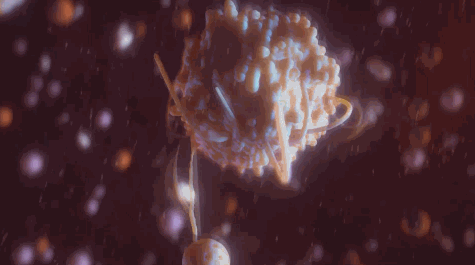

答案是噬菌体。

某种特殊的情况下,噬菌体入侵链球菌,改写了它的基因,但却并没杀死它。

由此产生的新型细菌反而拥有了极强的生存能力。

细菌、病毒、人类之间的纠葛暂告一段落,寄生虫与人类的羁绊同样精彩。